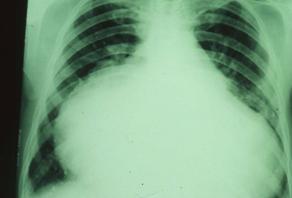

RIGETTO GRADO III A

INFEZIONE POLMONARE DA PNEUMOCYSTIS CARINII